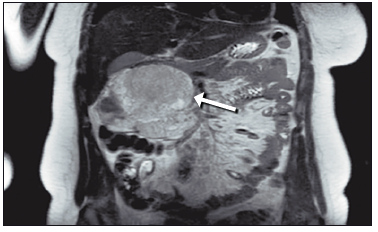

Los estudios de laboratorio, incluidos marcadores tumorales, se encontraron dentro de los parámetros normales. Se realizó una resonancia magnética nuclear (RMN) con contraste endovenoso, la cual evidenció una lesión pancreática en la región cefálica, de señal heterogénea, con áreas hiperintensas en T1 y realce heterogéneo postcontraste. La lesión, de 97 x 110 x 100 mm, no invadía estructuras adyacentes (Figura 1).

Figura 1. Imagen de resonancia magnética que muestra una lesión en la cabeza del páncreas (flecha blanca) que desplaza las estructuras adyacentes